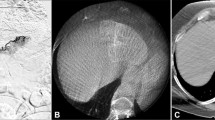

Geographical enhancement: correlating with cone-beam CT

Cone-beam CT has taken a major role in guaranteeing a successful treatment, by providing additional information during response assessments [16, 36].

A common finding, characteristic for Y90, is the presence of geographical enhancement with an extension greater than the treated tumor; this could be confused with active infiltrative tumor disease [40]. In RS, geographical enhancement usually presents with a characteristic wedge pattern. This wedge can be correlated perfectly to the pre-treatment cone-beam CT, reaffirming the relation of the enhancement with the treated segment. This enhancement may persist for months and, in some cases, will not completely disappear, but the overall segment will progressively scar and contract. It is a benign finding specific to Y90 and does not correspond to an adverse treatment reaction or tumor progression (Figs. 10, 11). “Geographical enhancement” was seen in 94% (58/62) of the patients in our review (Table 4).

A Pre-treatment contrast-enhanced MR image showing arterial hyperenhancing lesion (arrow). B Pre-treatment cone-beam CT that shows good targeting of the segment (arrows). C MR image at 1-month follow-up showing wedge-shaped geographical enhancement that correlates 1:1 with pre-treatment cone-beam CT (arrows). D 7-month image follow-up showing persistent geographical enhancement, scar formation, and segmental retraction corresponding to the treated area. (arrow)